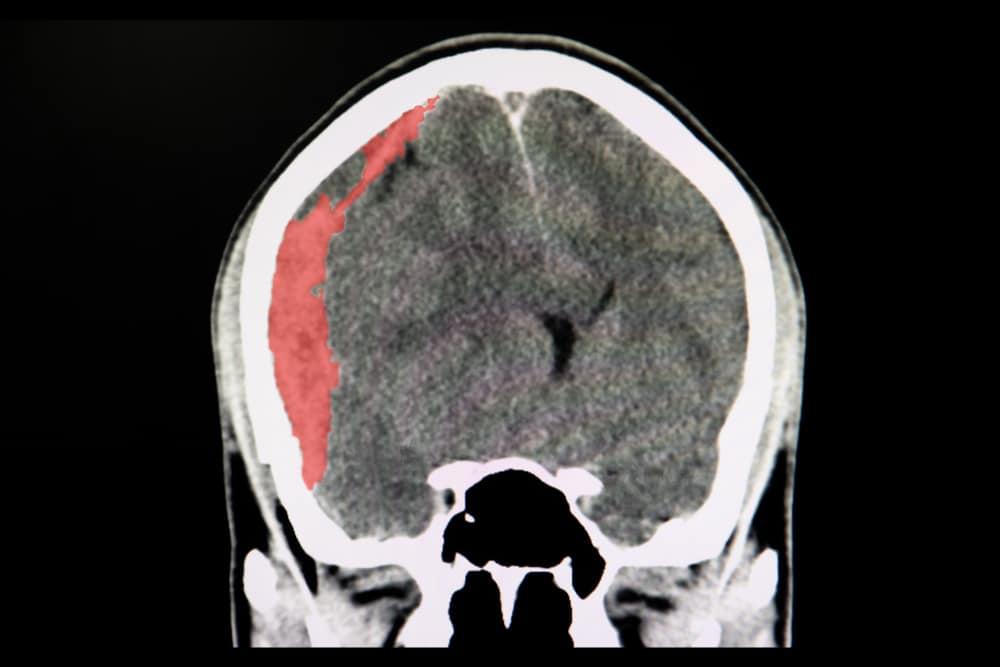

Não của con người được bao bọc bởi các lớp màng não, bao gồm màng cứng, màng nhện và màng mềm, sau đó mới tới xương sọ và da đầu. Khi mắc bệnh tụ máu dưới màng cứng (hay còn gọi là xuất huyết dưới màng cứng), máu sẽ bị tích tụ ở khoảng trống ở giữa màng cứng và màng nhện.

Người bệnh nhập viện sau khi bị chấn thương đầu thường được làm chẩn đoán hình ảnh đầu như chụp cắt lớp vi tính (CT) hoặc chụp cộng hưởng từ (MRI). Những kiểm tra hình ảnh này có thể giúp bác sĩ phát hiện sự tồn tại của tụ máu dưới màng cứng. Chụp MRI ưu thế hơn một chút so với chụp CT trong khả năng phát hiện tụ máu dưới màng cứng nhưng chụp CT lại nhanh và thường sẵn có hơn.